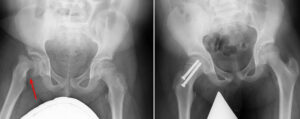

(Left) Preoperative X-ray of an unstable SCFE . (Right) Postoperative X-ray shows that the femoral head has been manipulated back into place and screws have been inserted to hold it in place.